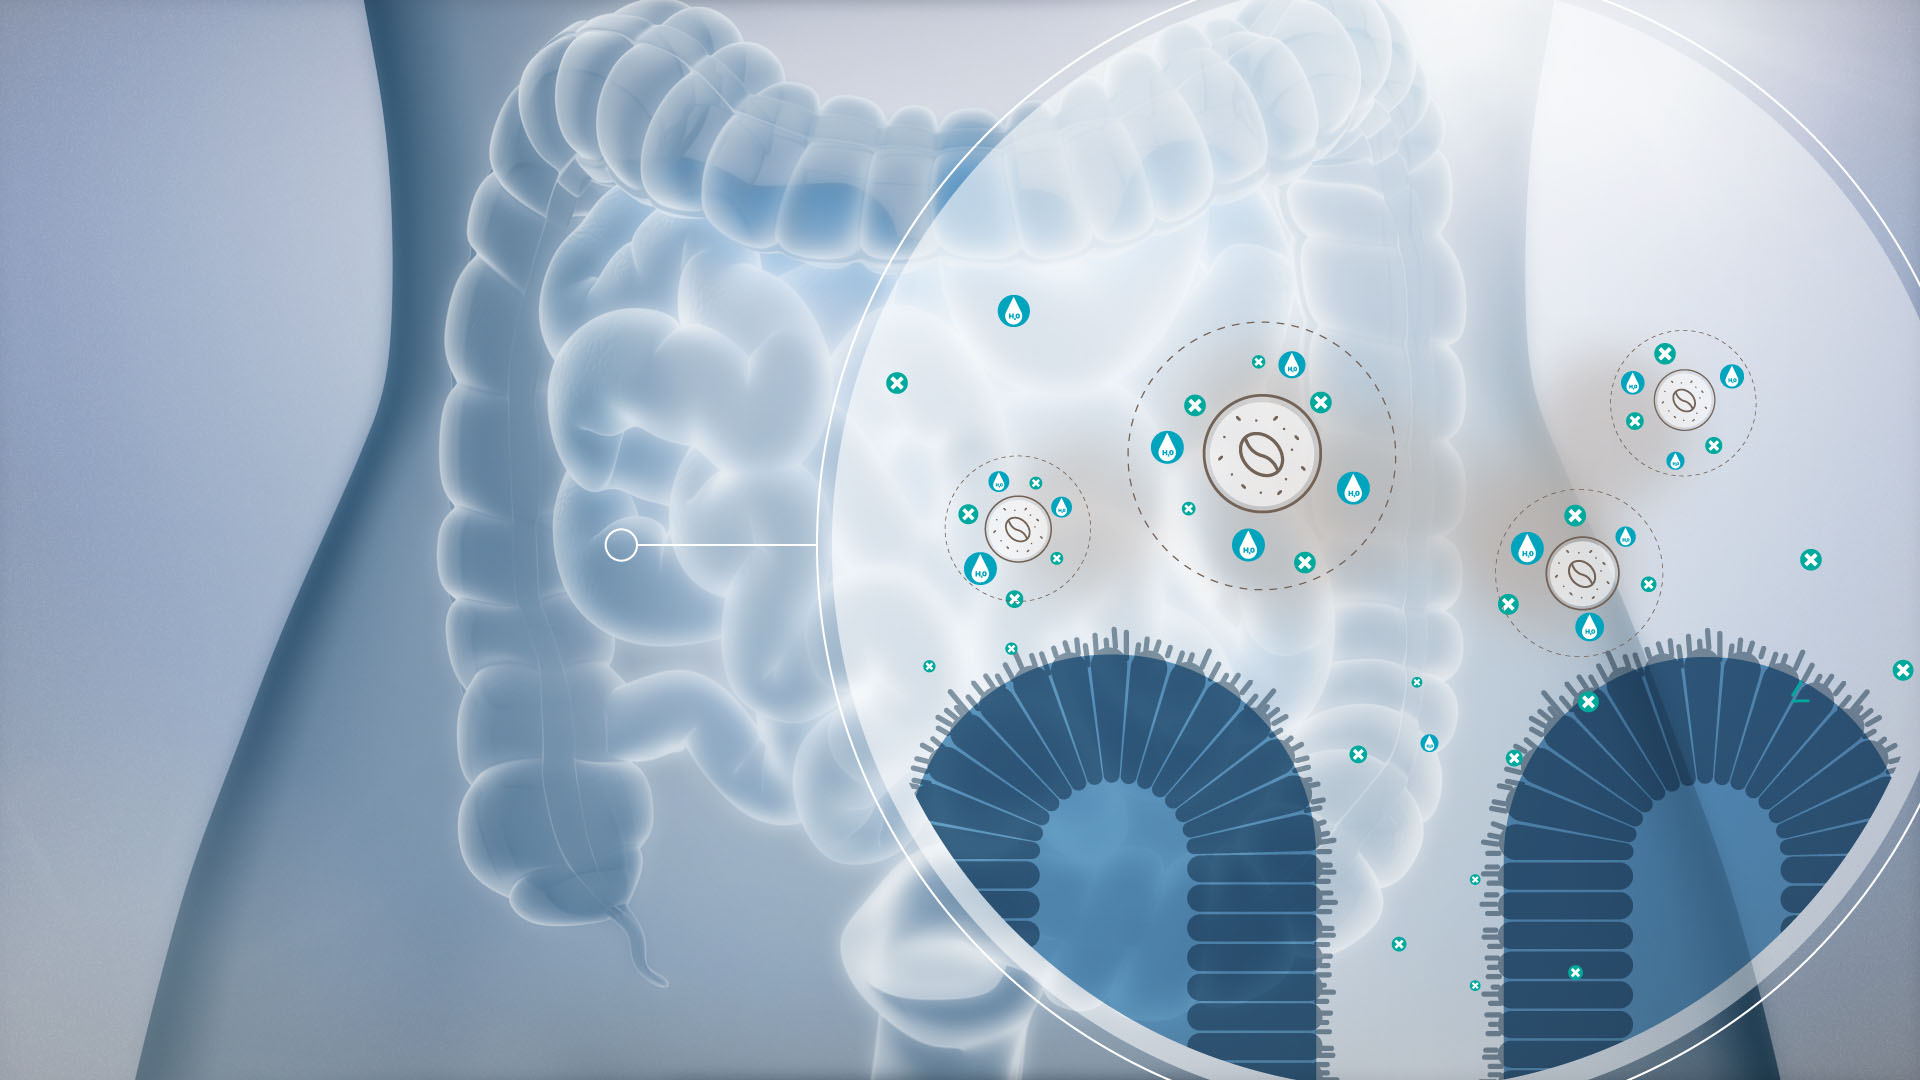

3D-WORKS

Manchmal muss es einfach 3D sein. Auch wenn sich in unseren 2D Animationen mehr 3D versteckt als man denkt, sind unsere realistischen Renderings immer etwas Besonderes. Speziell auf dem Gebiet der Medizin haben wir schon viele Projekte in 3D realisiert. Auch wenn wir davon hier nur wenig öffentlich zeigen dürfen.